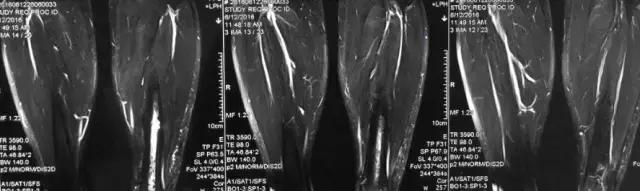

影像检查

诊断:感染。 检查:膝关节MRI,确认伤口窦道是否与髓腔相通。 治疗:1、血沉和C反应蛋白正常,目前无需特殊处理。 2、如果窦道反复出现或血沉和C反应蛋白升高可考虑手术。如证明窦道与髓腔相通,需行扩髓。

核磁示中下段骨髓炎,上面切口处流脓,请问张主任你的意见要上手术吗?

1、是具备手术指征了!也就是说可以手术。 2、并不是必须马上手术。不发热,不红肿、化验都正常也可以换药口服抗生素。